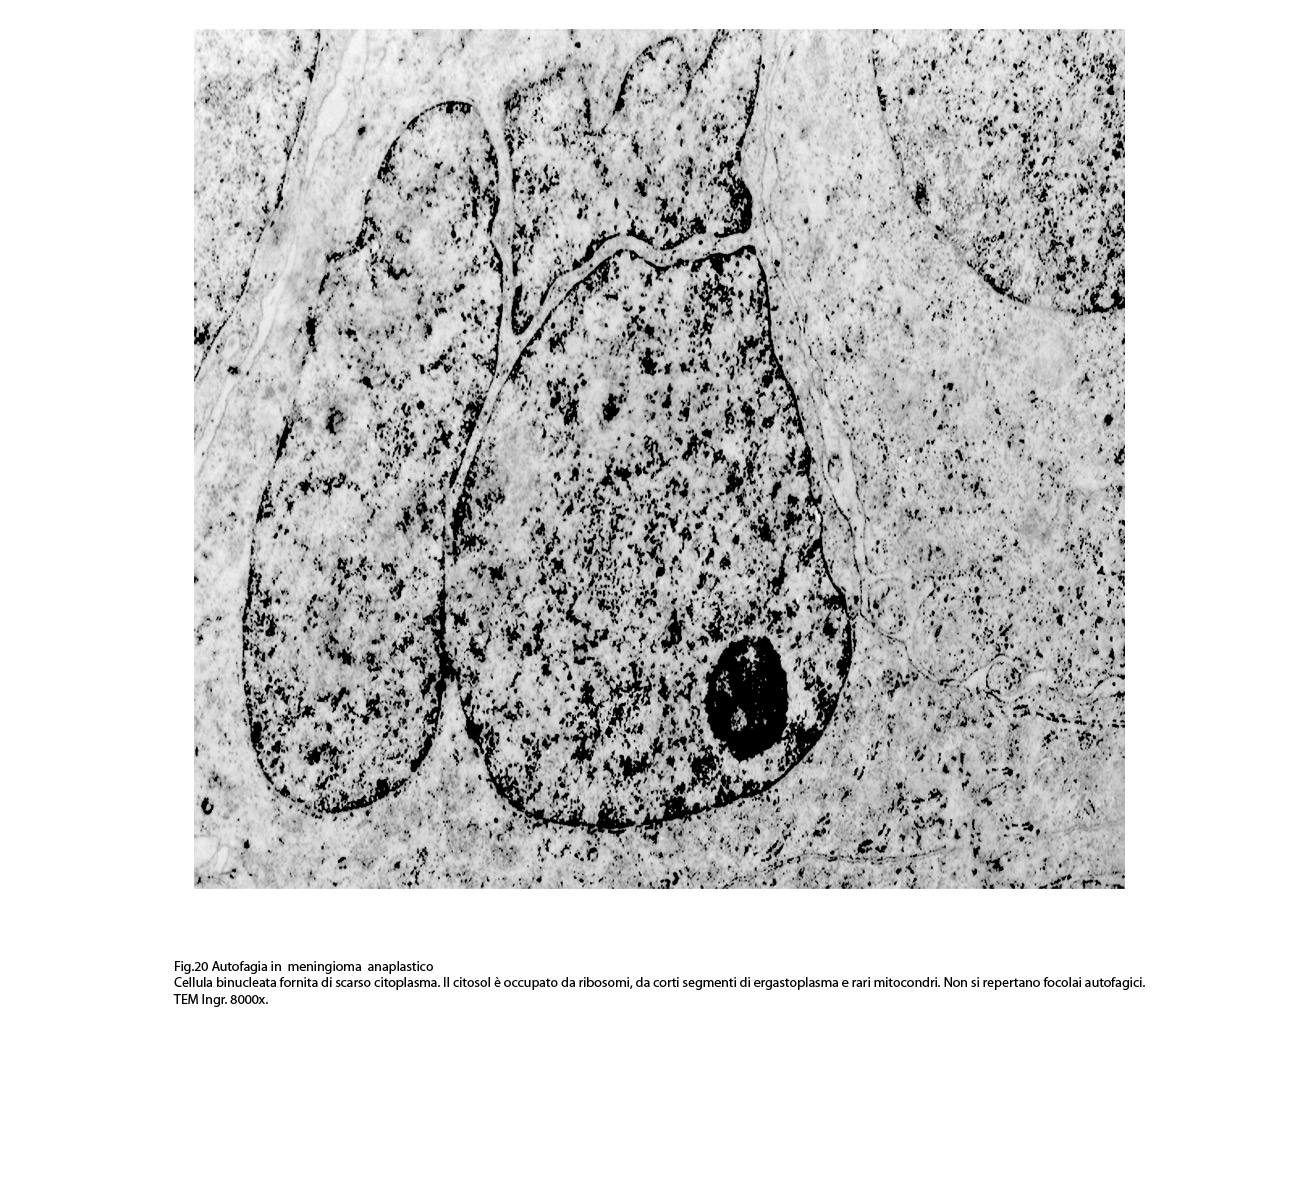

B) FOCOLAI DI AUTOFAGIA IN MENINGIOMI ANAPLASTICI

La popolazione cellulare dei meningiomi anaplastici è data da elementi di piccole e medie dimensioni che si dispongono spazialmente in aggregati informi. Ciascuno di essi ha una forma irregolarmente cuboide o poligonale e soprattutto è caratterizzato da una esigua quota citoplasmatica esigua e da una voluminosa massa nucleare.

Al microscopio elettronico,il citoplasma appare compatto ed il citosol contiene pochi mitocondri, scarso reticolo endoplasmatico ed ergastoplasma, discrete quote di ribosomi liberi e di microtubuli.

Molto frequentemente si riscontrano elementi i quali evidenziano una condizione di cellula binucleata.

Le numerose osservazioni ultrastrutturali condotte su casi di meningiomi anaplastici hanno evidenziato in modo ripetitivo gli abituali caratteri di cellule con tale morfologia e in nessun campo hanno evidenziato focolai riferibili a processi di autofagia.